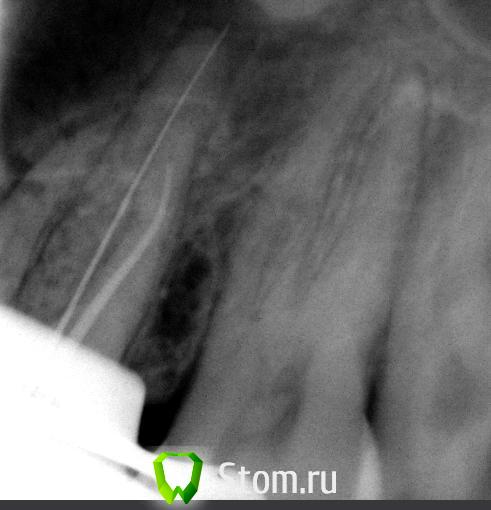

Ferny Опубликовано 30 марта, 2012 Поделиться Опубликовано 30 марта, 2012 помогите пожалуйста, дорогиэ коллеги! зыб 26 периодонтит. раширяла протейперами С1,Сх и потом делала рентген с иголками после показаний апекс локатора. если верит апекс локатору то вот рентген , палатоиналняй за верхущку на 1 мм, а букодисталний канал вобще не доходит до апекса, хотя апекс локатор всё показал . переделала рентген, в палатиналном на 1 мм менще длину поставила а на букодисталном поставила на 2 мм болще. посмотрите...меня интересует букодисталняй...с длиной 19 мм апекс локатор 4тото как то неопределённо показявает то 0,4-0,5...нужно ли в букодисталном идти далще или оставитй так как естй и расщирят его далще? спасибо Ссылка на комментарий